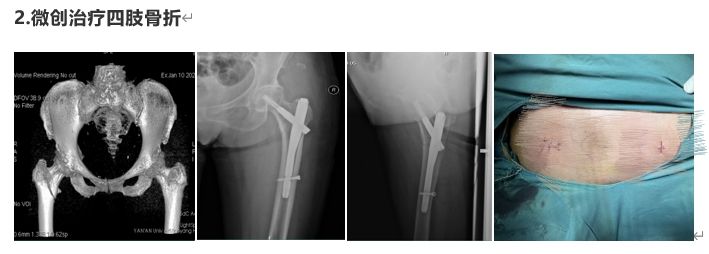

部分病例展示

延安大學咸陽醫院骨科二病區是以手足顯微外科、慢性創面修復、關節外科、創傷骨科、小兒骨科為主要研究方向的專業化科室。現有床位36張,醫護人員20人,其中主任醫師1名,副主任醫師2名,中級職稱3名,住院醫師2名。